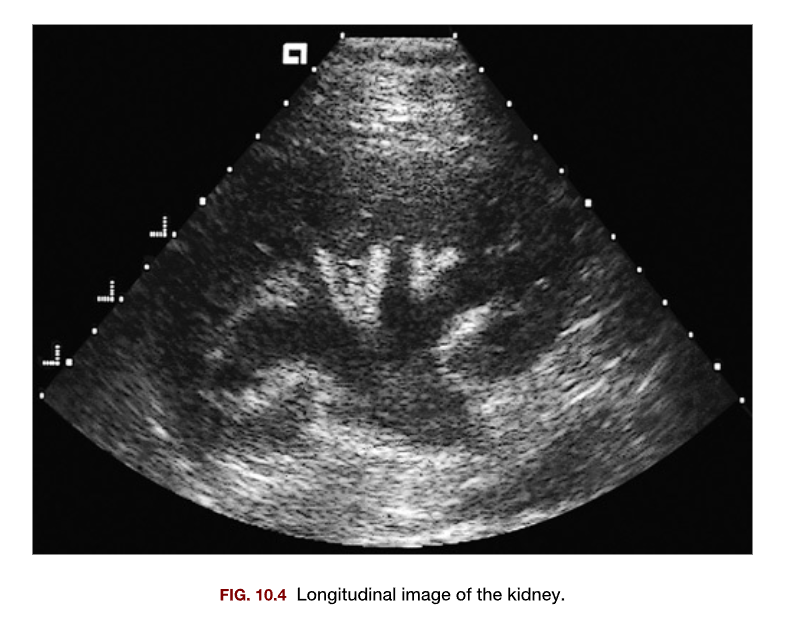

Which of the following conditions is most likely demonstrated in this sonogram of the kidney?

1. Pelviectasis

2. Pyelonephritis

3. Nephrolithiasis

4. Hydronephrosis

A

1. Hydronephrosis

Which of the following anatomic variants is most likely identified in this sonogram 1. Renal duplication 2. Crossed fused ectopia 3. Junctional parenchymal defect 4. Hypertrophied column of bertin

4. Hypertrophied column of bertin